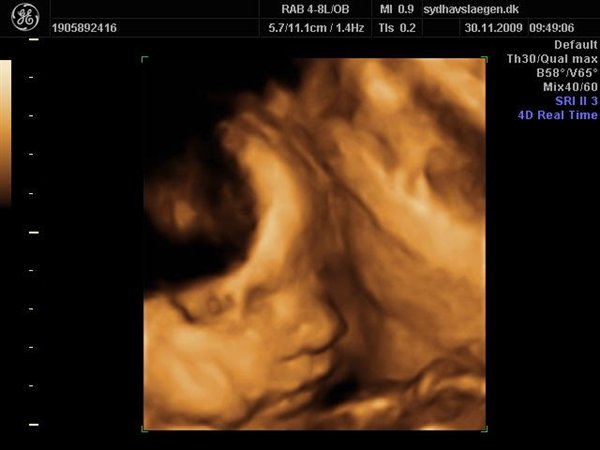

Da jeg snakkede med hende i dag sagde hun at fra uge 27 til og med uge 31 var det bedste tidspunkt at få det gjort....

Vi skal give 1400 kr for 45 minutters total gennem scanning, hvor hun fortæller, undersøger babyen fra top til tå, laver vægtskøn også får vi billeder og dvd med hjem.... Og ja det er da mange penge, men min forlovede har haft en masse vikar timer den her mdr, også sagde han at han syntes vi skulle bruge de penge på noget vi normalt ikke ville have gjort. Han sagde egentlig at jeg kunne gå ud og shoppe for dem, men jeg har termin om ti uger, så gider ærlig talt ikke bruge penge på nyt graviditets tøj, så hellere det her som vi egentlig havde valgt fra pga prisen, men som vi begge to rigtig gerne vil....